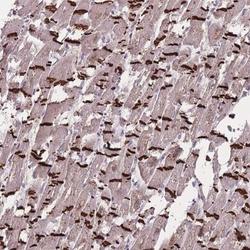

Supportive validation

- Submitted by

- Novus Biologicals (provider)

- Main image

- Experimental details

- Immunohistochemistry-Paraffin: TMEM232 Antibody [NBP2-14682] - Staining of human heart muscle shows strong positivity in intercalated discs of myocytes.